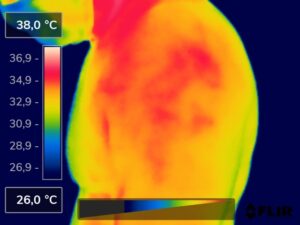

Como na sequência de termogramas abaixo de um paciente do sexo masculino, de 44 anos, sem comorbidades e praticante de atividade física que apresentou fortes dores em braço esquerdo (com irradiação para antebraço) após treino de musculação. Esta dor chegou a ser incapacitante, pois impossibilitava inclusive o paciente a realizar atividades de vida diárias como pegar um copo de água.

Após a realização de uma Análise Termofuncional©®, foi detectado alterações térmicas em “linha”, margeando as fibras musculares e tendíneas inferiores (insercionais) bicipitais. Estas alterações também aventaram a hipótese de dilatação venosa, por alguma reação inflamatória local. Foi realizado então aplicação de laserterapia através da Técnica Termoguiada, que acabou por promover a completa analgesia em 24 horas após aplicação.